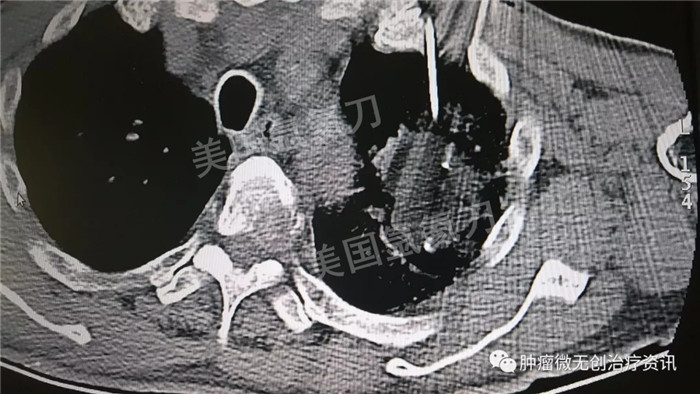

民航总医院氩氦刀冷冻消融治疗肺癌

63岁男性患者,发现左肺占位1天入院,伴多发骨转移及肺内转移,行氩氦靶向治疗减瘤,同时穿刺取病理活检。